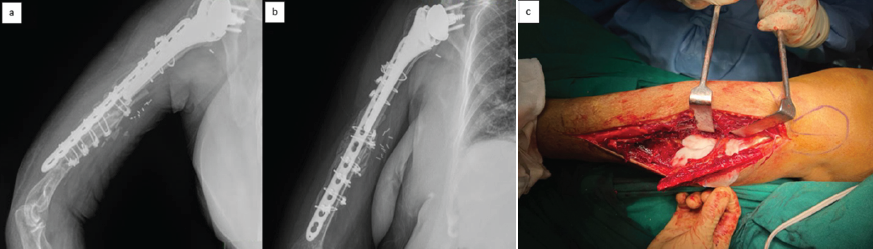

A standard open reduction and internal fixation was utilized to treat the contralateral distal radius fracture. Three weeks later patient presented with a history of a trivial trauma (twisting injury while applying an arm sling) and, on evaluation, was diagnosed to have a displaced fracture with a failed implant (Figure 3a,b).

Figure 3: Anteroposterior and lateral radiographs showing failed osteosynthesis of the periprosthetic fracture with pulled-out implant from the distal fragment and displaced fracture (a and b). Intra-operative clinical photograph showing failed osteosynthesis of the periprosthetic fracture with pulled out implant via an extended anterolateral approach (c).

Surgical technique

The patient was positioned supine with a side arm table. An extended anterolateral approach combined with a medial incision for additional exposure of the brachial vasculature was chosen after discussion with the vascular surgeon so as to enable safe and effective vascular anastomosis between the brachial vessels and the peroneal vessels of the graft. The implant (locking compression plate [LCP] 4.5 mm) was found to be completely backed out (Figure 3 c) from the distal fragment with stripping of all four locking screws. The radial nerve was completely isolated from the plate, protected, and a safe exit of the entire implant was carried out. A 10 cm segment of fibula with an associated vascular pedicle was selected, shaped appropriately, and interposed in the gap between reduced proximal and distal fragments in such a way that good contact is made between the host bone and the graft. The remaining portion of the fibula was split longitudinally and used on either side of the construct to augment the fixation. Finally, a 4.5 mm LCP was used along with an encirclage wire system to complete the procedure. The case was handed over to the vascular surgeon to complete the microvascular anastomosis. Good blood flow in the graft was observed post-anastomosis. Fluoroscopy images showed near anatomical reduction of the fracture with a well-placed fibula graft (Figure 4a, b) with excellent contact all over.